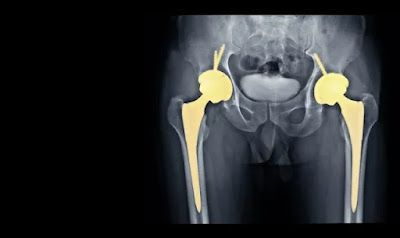

It is essential to grasp the fundamentals of hip replacement surgery before delving into the specifics of postoperative rehabilitation. This surgical procedure replaces a fractured or injured hip joint with an artificial implant to alleviate pain and increase mobility. The objective of both conventional hip replacement and minimally invasive surgery is the same: to improve quality of life and restore function.